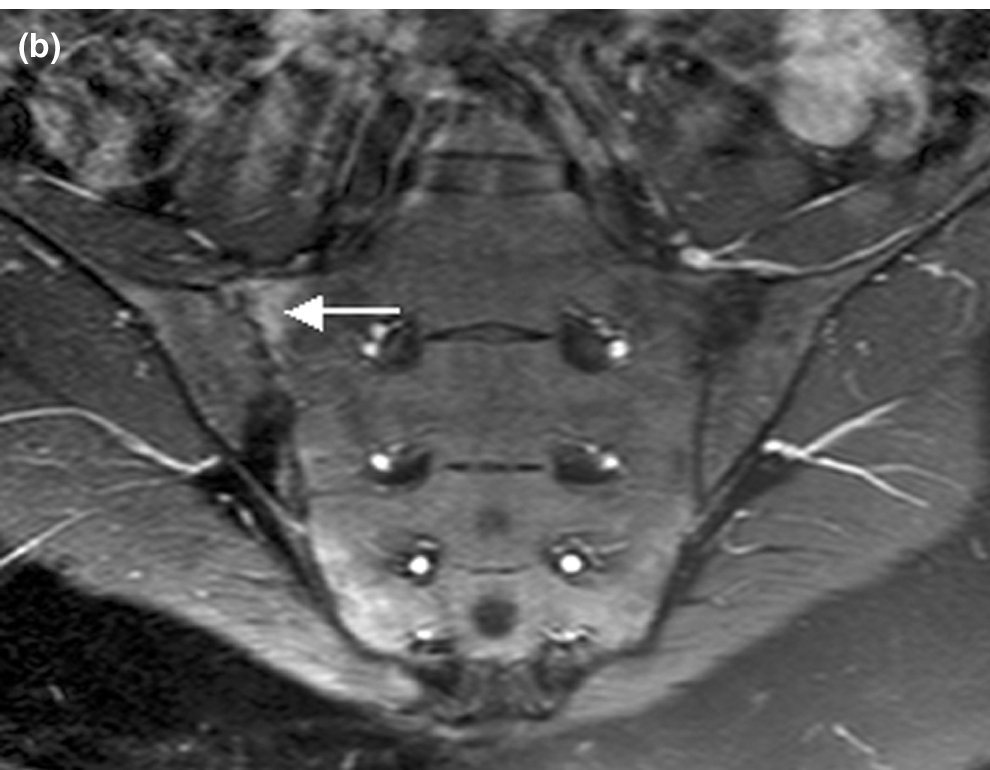

The sacroiliac joints can be imaged using MRI, mainly to exclude unusual pathologies (Infection, Stress Fracture).